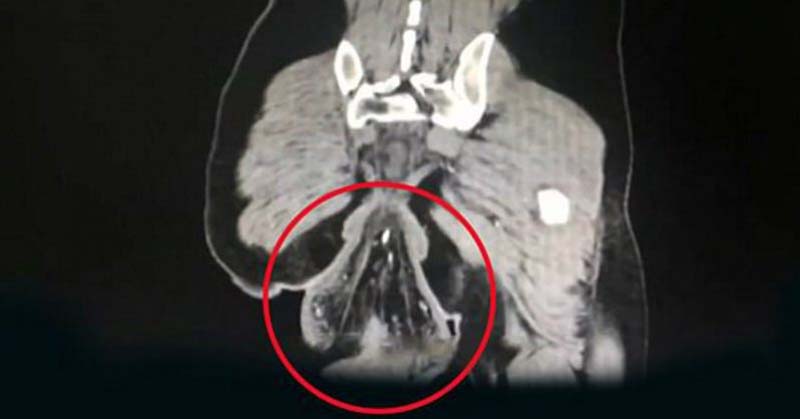

Period pain is common for a lot of women. Bloating, nausea and cramps are all part of the package that comes with menstruating for the majority. But when the pain becomes unbearable to the point of passing out- that definitely is something to be concerned with. Undiagnosed Dermoid Cyst: Calle Hack’s “Little Monster” Growing up,...